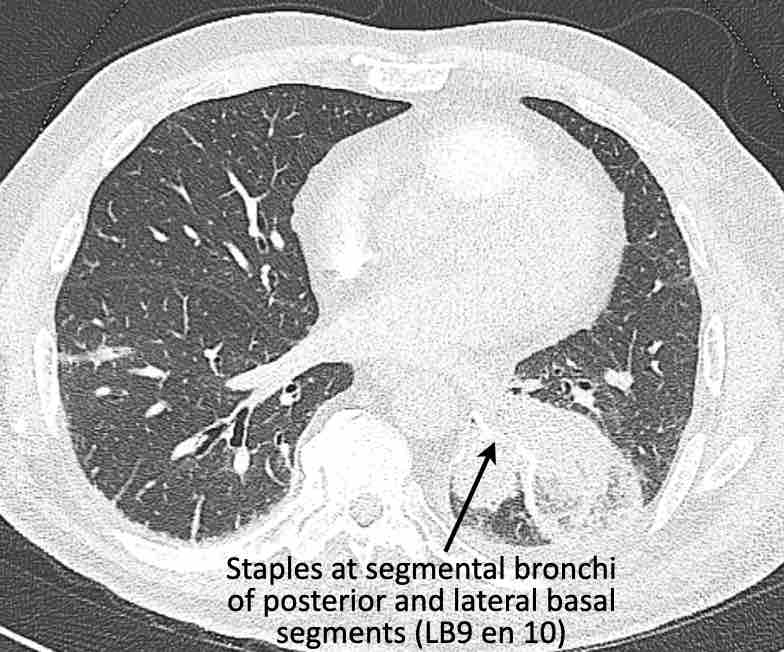

Hình ảnh

Cuộn qua các hình ảnh.

Theo dõi các phế quản của thùy dưới phổi trái cho thấy nhánh phân thùy đầu tiên của thùy dưới phổi trái còn thông; đó là phế quản phân thùy đỉnh.

Các ghim phẫu thuật nằm tại vị trí của các phân thùy đáy sau và đáy bên (LB9/10), vốn thường được cắt bỏ cùng nhau.

Do đó, phân thùy phổi có hình ảnh kính mờ và đông đặc phải là phân thùy đáy trước của thùy dưới phổi trái (LB8).